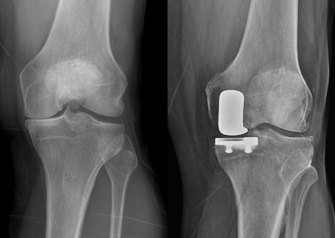

So, when pain in both of his knees began to affect his ability to sleep, comfortably work, ride a motorcycle, or do ordinary chores, he began to do his research. It was then that he learned that there were two types of knee replacement procedures: a total and a partial knee. Unlike a complete knee replacement, a partial knee replacement could be performed if only one part of the knee was affected by arthritis. He learned that potential benefits of a partial knee include a shorter recovery time, lower risks around the time of surgery, and a knee that feels more normal and natural since all of the ligaments are preserved.

“Mr. Corn was a good candidate for a partial knee replacement as he had arthritis predominantly on this inside of his knee, good flexibility, and normal-feeling ligaments,” Dr. Della Valle explains.